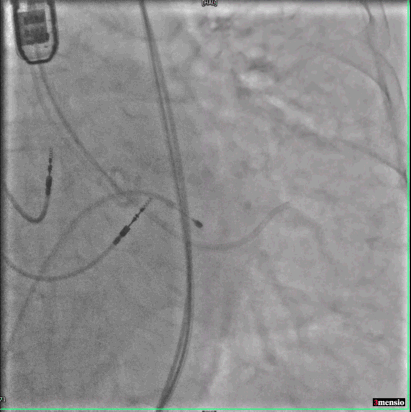

阿婆肾脏功能受损,心衰严重,无法耐受造影剂,做不了传统TAVR手术前评估最重要CT扫描环节。危机时刻,深圳市人民医院心内科心脏彩超室李江华医生,用超声评估的方式代替CT扫描,用超声圆满完成术前评估,体现了深圳市人民医院的超声测量的精确性和可靠性。

跨瓣